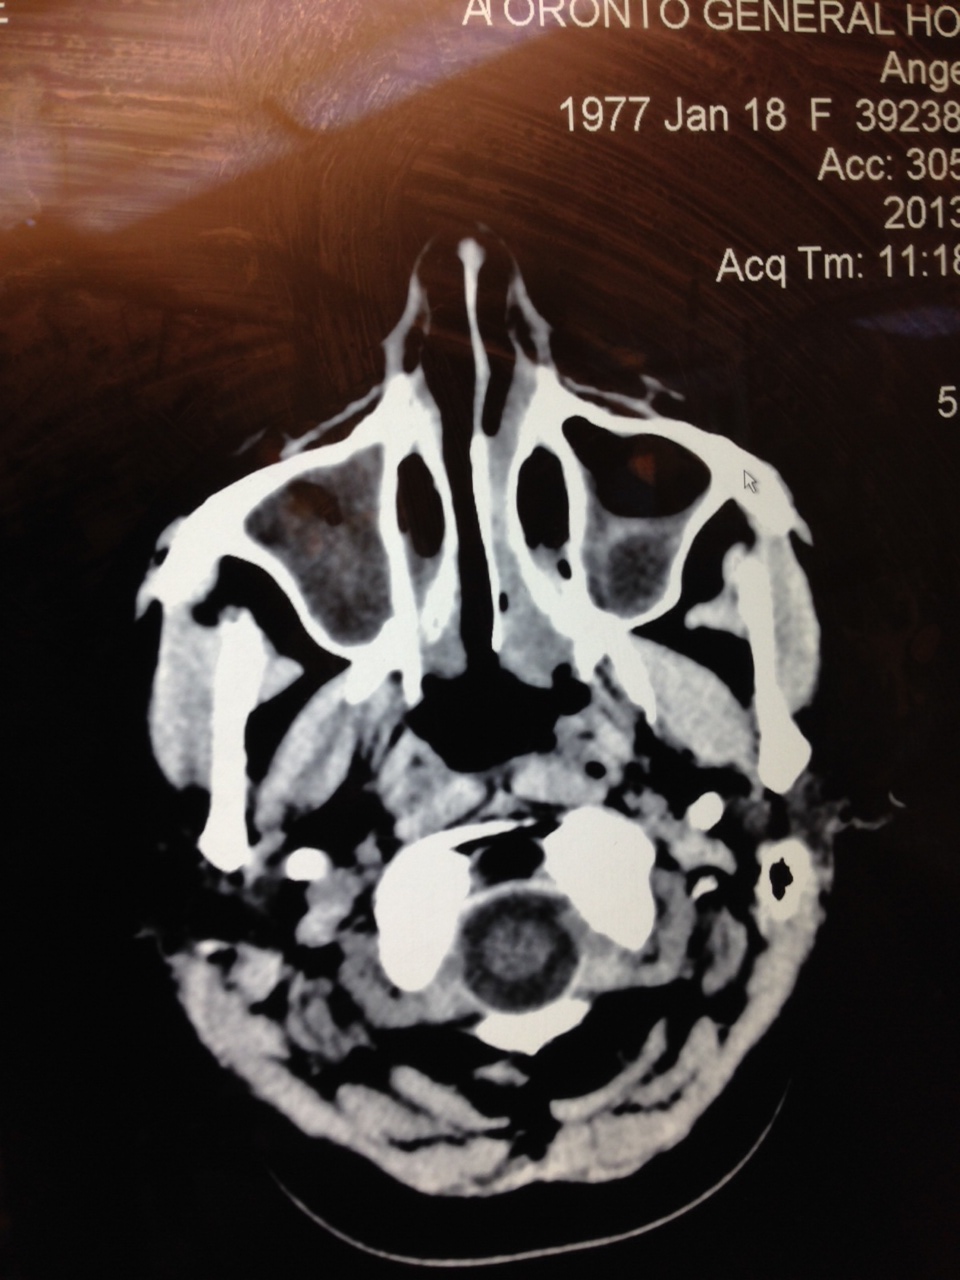

- A spinal tap to test fluid and a head surgery to biopsy the brain and lining were part of the exploration/discovery.

- The first week of 2014 set the stage for a post-sinus infection diagnosis. Cancer. Again. This time racing through the brain’s lining.